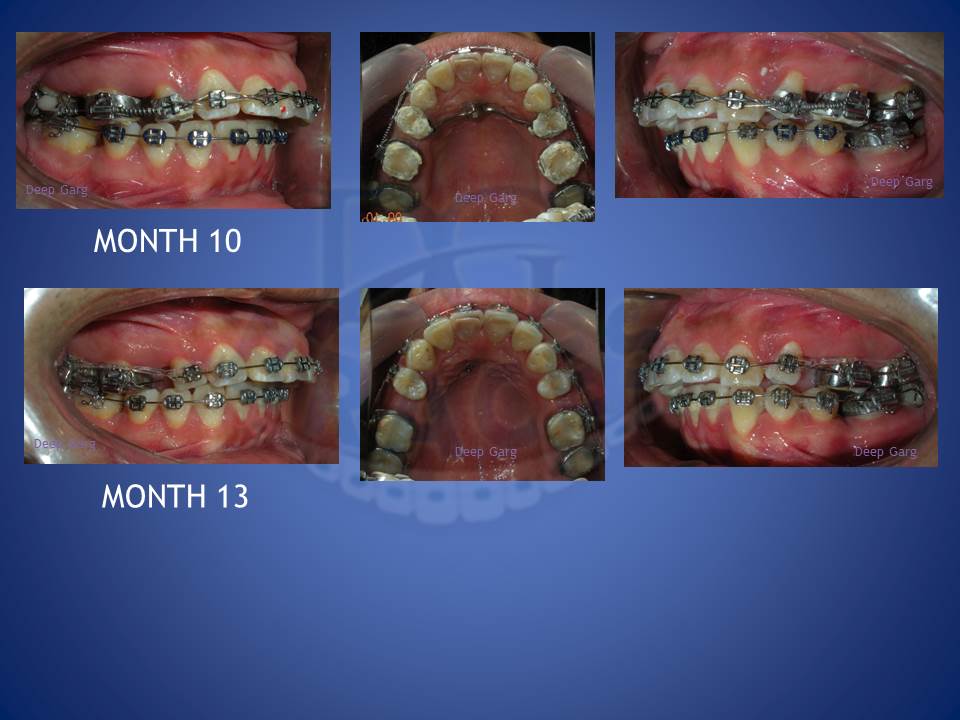

3.Molar distalisation though difficult can be very well done in cases where excessive spaces are required and no extractions can be afforded. Here a palatal Miniscrews was used and distalisation was done with coil springs.